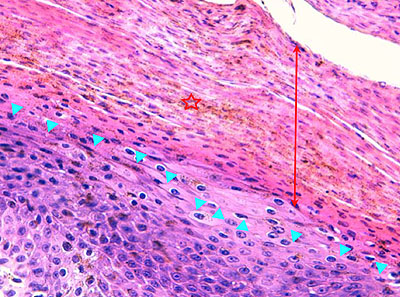

Photo 4 (Hémalun Eosine X 100) : aspect bleu de l’épiderme pour hyperplasie des couches basales, qui dessinent des crêtes épithéliales allongées, filiformes, ramifiées et branchues, peuplées de cellules basales hyperbasophiles. L’épiderme est multifocalement exulcéré. L’infundibulum folliculaire visible présente une hyperkératose parakératosique sans visualisation nette d’une couche des grains. Le derme montre une discrète angiectasie des capillaires du plexus superficial ainsi qu’un discret infiltrat inflammatoire périvasculaire superficial.

Légendes de la Photo 4 :

- Triangles bleus foncés : contours de crêtes épithéliales allongées, filiformes, ramifiées et branchues, peuplées de cellules basales hyperbasophiles.

- Triangles bleus clairs : exulcération épidermique

- Flèche rouge : parakératose épidermique et folliculaire

- Étoile rouge pleine :Le derme est faiblement à modérément inflammatoire (infiltrat mononucléé)

- Étoile rouge creuse : angiectasie des capillaires sanguins

- Étoile bleue claire : glandes sébacées